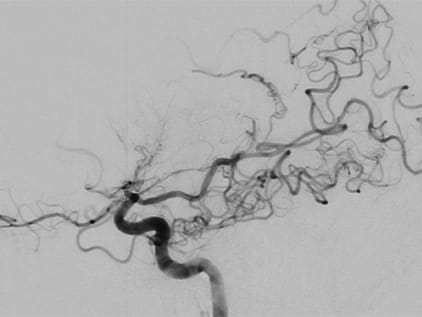

One study that is helpful in diagnosis of moyamoya disease is the cerebral angiogram. This is a test in which dye is injected into your brain to help doctors visualize the blood flowing to the brain. The images will show any blockage and also will allow the doctors to see the cluster of tiny blood vessels at the base of the brain that is the telltale sign of moyamoya disease.

Moyamoya scan